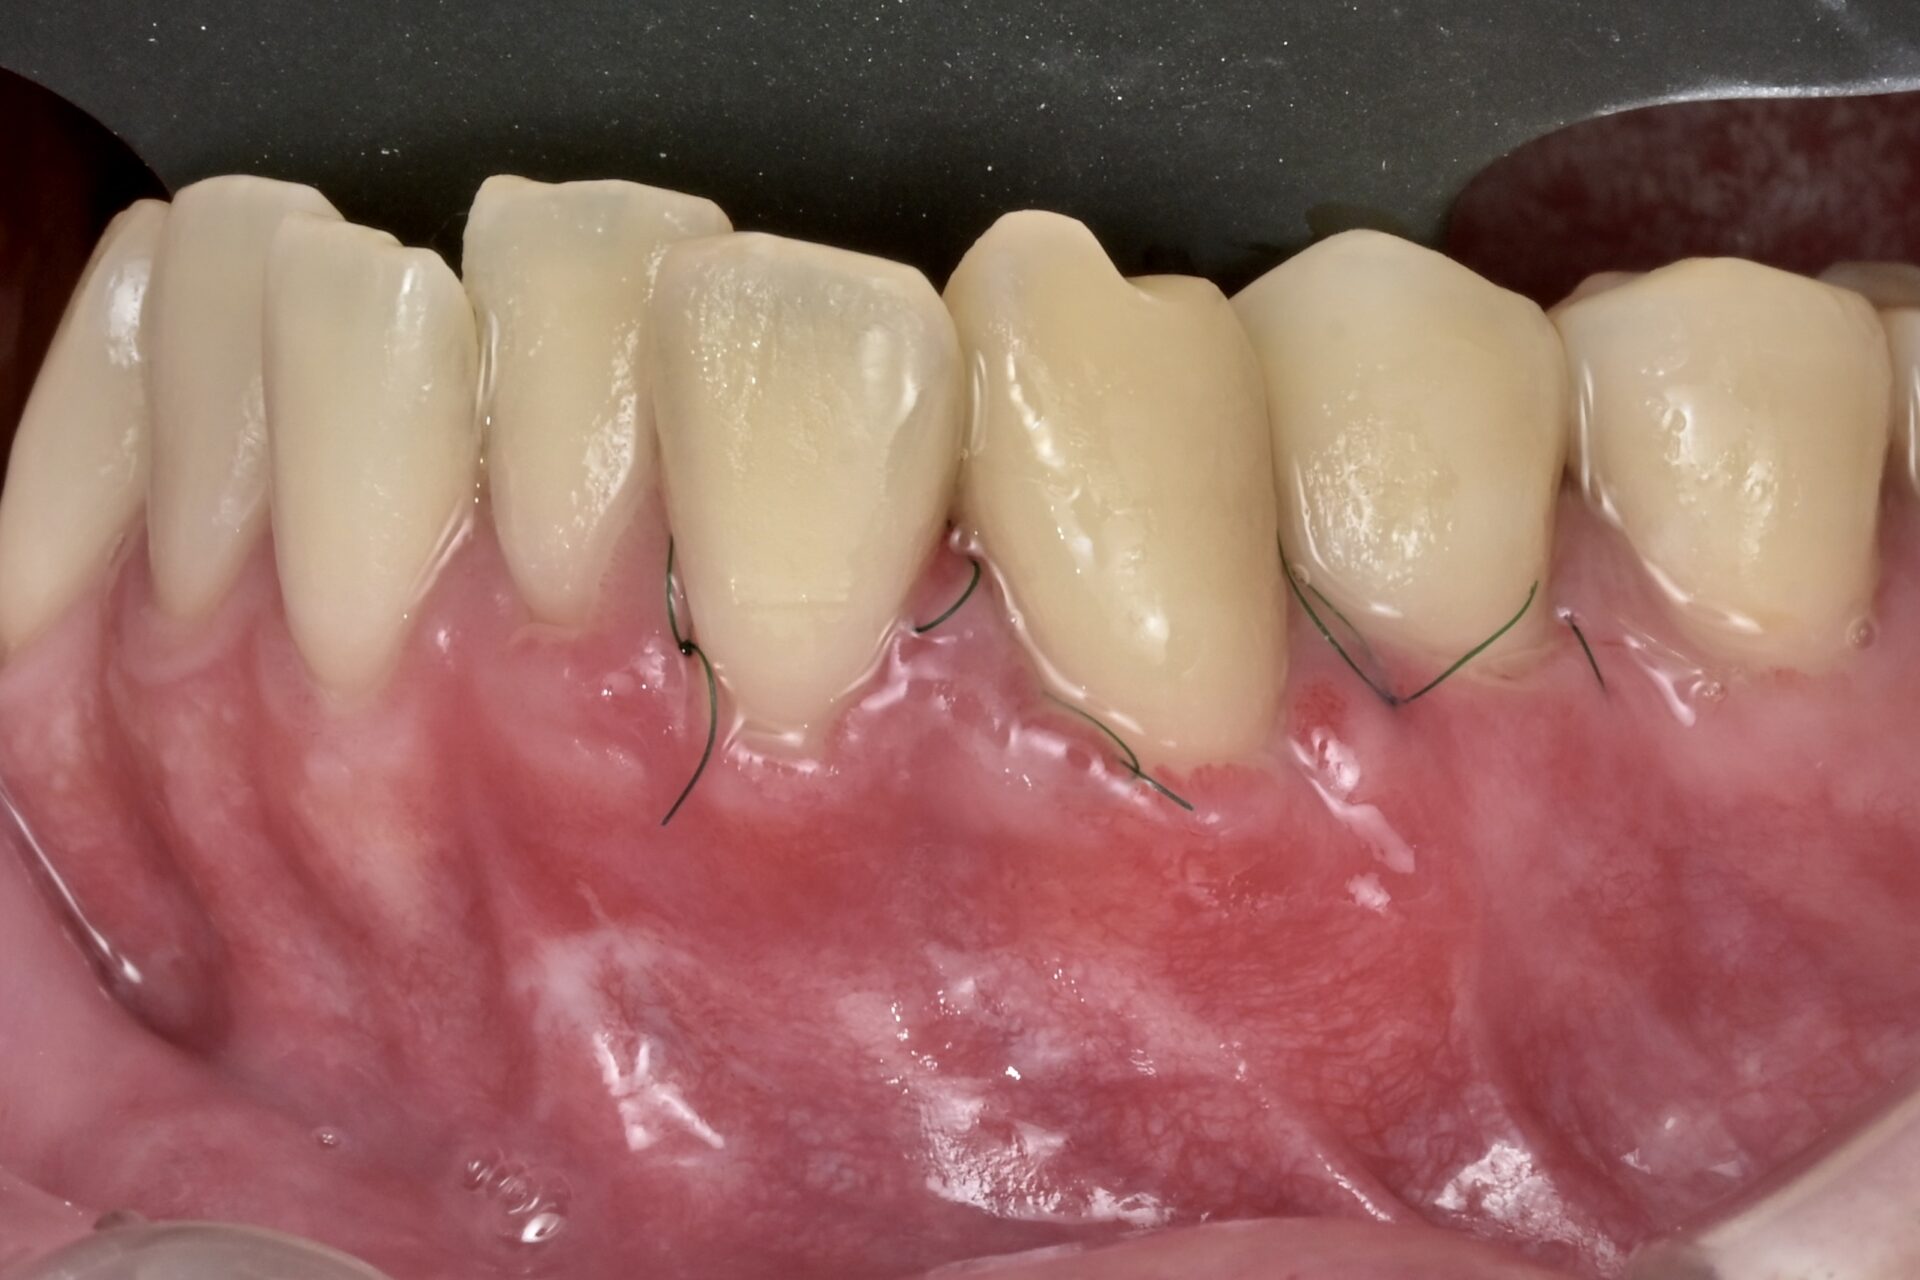

術後(SATT)

根面に歯周組織再生能力のあるエムドゲインを塗ります。その後に口蓋部から結合組織を採取して露出根面に吸収性の糸で縫い付けます。今回はSATTという切開縫合の術式を用いました。 -